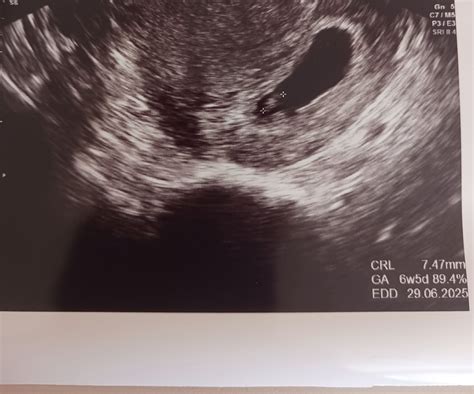

Určenie dátumu pôrodu

Je možné, že dátum pôrodu zobrazený na monitore sa bude líšiť od toho, ktorý vám predpovedal lekár doteraz. Ani tento nový termín však nemusí byť definitívny, pretože môžu existovať určité odchýlky. Niektoré bábätká rastú v istých obdobiach rýchlejšie, neskôr sa ich rast spomaľuje alebo naopak. Napriek tomu by sa mal tento termín pohybovať v rozmedzí plus-mínus 2-3 dní.